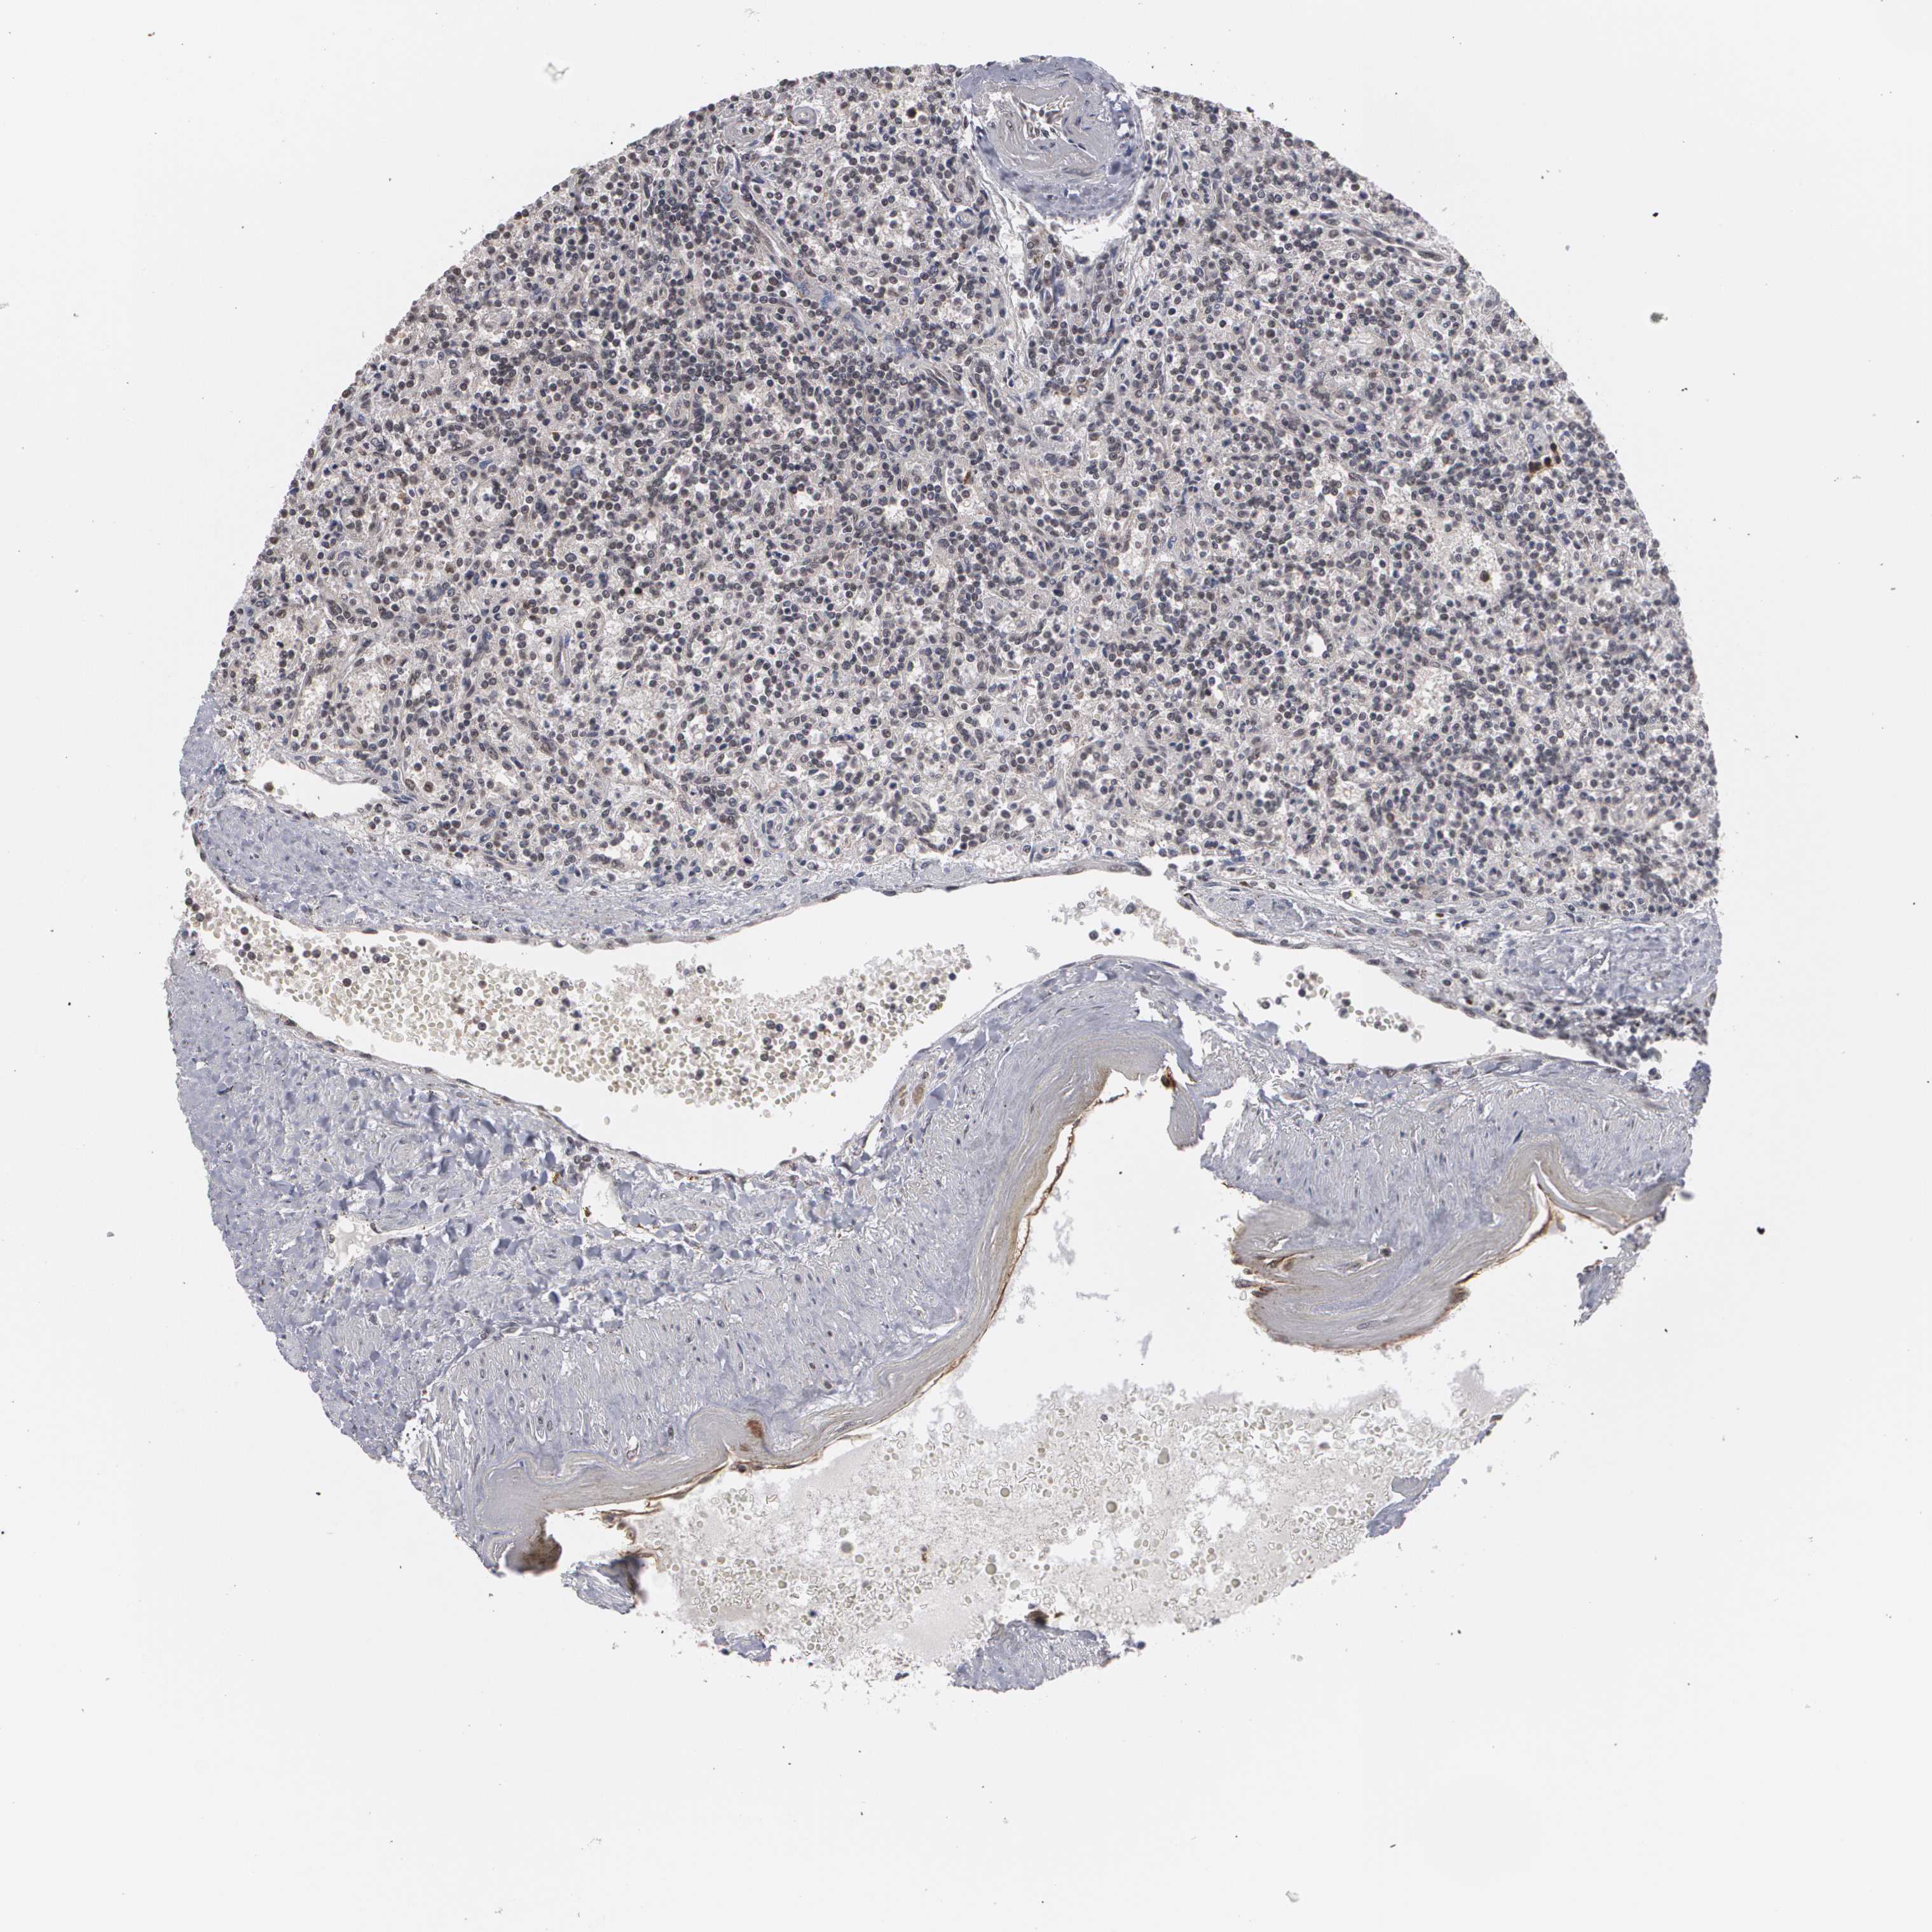

LYMPHOMA - Protein expressioni

A mouse-over function shows sample information and annotation data. Click on an image to view it in a full screen mode. Samples can be filtered based on level of antibody staining by selecting one or several of the following categories: high, medium, low and not detected. The assay and annotation is described here.

Antibody staining in the annotated cell types in the current human tissue is reported as not detected, low, medium, or high, based on conventional immunohistochemistry profiling in selected tissues. This score is based on the combination of the staining intensity and fraction of stained cells.

Each image is clickable and will lead to virtual microscopy that enables deeper exploration of all samples and also displays staining intensity scores, fraction scores and subcellular localization as well as patient and tissue information for each sample.

Antibody HPA001665

Staining

High

Medium

Low

Not detected

Intensity

Strong

Moderate

Weak

Negative

Quantity

>75%

75%-25%

<25%

None

Location

Nuclear

Cytoplasmic/membranous

Cytoplasmic/membranous,nuclear

Malignant lymphoma, non-Hodgkin's type, High grade

Malignant lymphoma, non-Hodgkin's type, Low grade

Hodgkin's disease, NOS